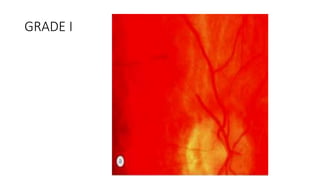

GRADE I